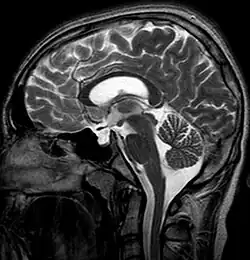

Die Sella turcica (deutsch: „Türkensattel“) stellt eine Schädelgrube mittig im Bereich der mittleren Schädelgrube (Fossa cranii media) dar, in der normalerweise die Hypophyse liegt, die zahlreiche Hormone bildet und damit Vorgänge wie Wachstum, Fortpflanzung und Stoffwechsel reguliert.

Beim Empty-Sella-Syndrom findet sich jedoch keine typische Form der Hypophyse in dieser Schädelgrube, sondern es kommt zu einer Hernien-artigen, von Liquor cerebrospinalis angefüllten Ausweitung des Subarachnoidalraums (Arachnoidozele) in die Sella turcica hinein. Dadurch wird die Hypophyse auf den Boden der Sella turcica gedrückt und erscheint wie „ausgewalzt“. Als Folge der Kompression der Hypophyse kann es zu endokrinen Störungen kommen.[1]

Morphologisch zeigt sich innerhalb einer häufig erweiterten Sella eine schalenartig umgestaltete, an den Rand verdrängte und druckatrophische Hypophyse.[1]

Allgemein liegt ein „partielles“ Empty-Sella-Syndrom vor, wenn die Sella turcica zu höchstens 50 % mit Liquor gefüllt ist, und ein komplettes Syndrom bei mehr als 50 % Liquorfüllung.